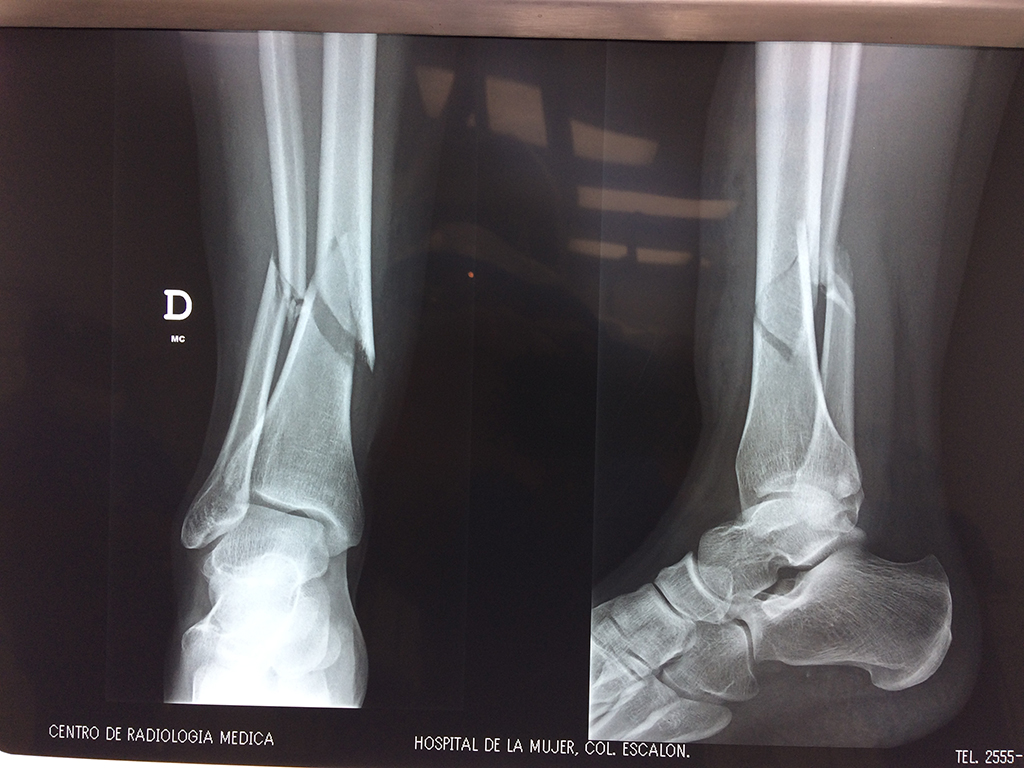

Calcaneo - Perone y Tibia

Aunque cada uno de estos huesos puede fracturarse por separado, normalmente la rotura es una lesión que se produce de forma conjunta

La mayor parte de las roturas implican a la parte proximal del hueso (parte del hueso próximo a la rodilla) o a la parte distal (parte del hueso cerca del tobillo).

Debido a la fina cobertura de piel que recubre la tibia y el peroné, las fracturas generalmente son abiertas, es decir, el hueso roto rasga la piel, atravesándola. Las fracturas de tibia y peroné generalmente se producen por un fuerte impacto o torsión.